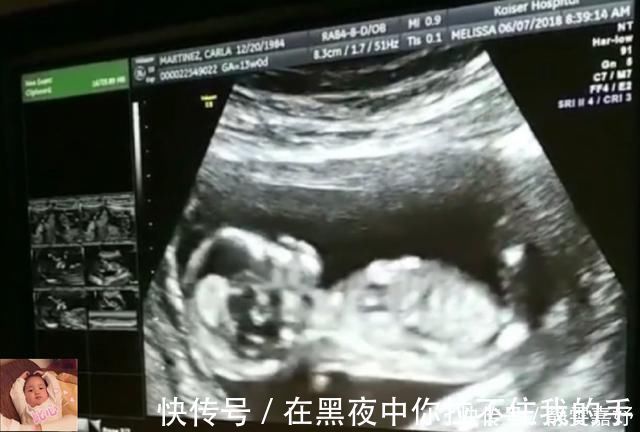

文章插图

4)打个哈欠

11周后胎宝宝,已经学会了打哈欠,吃完饭后,胎宝宝有些困了,打个哈欠表示自己要睡觉了哦。